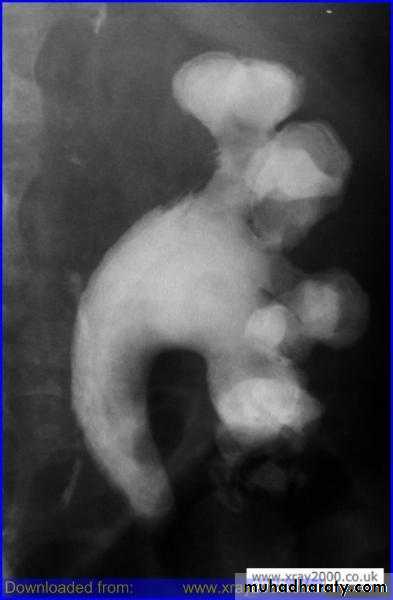

ureteroceles

These are submucosal dilatations of the intramuraldistal ureter. They often project into the bladder lumen

There is a female preponderance of approximately 4 to 1.

On IVU the ureterocele can be seen as a contrast-filled structure with a thin smooth radiolucent wall surrounded by contrast containing urine in the bladder. This has been described as a cobra's head appearance